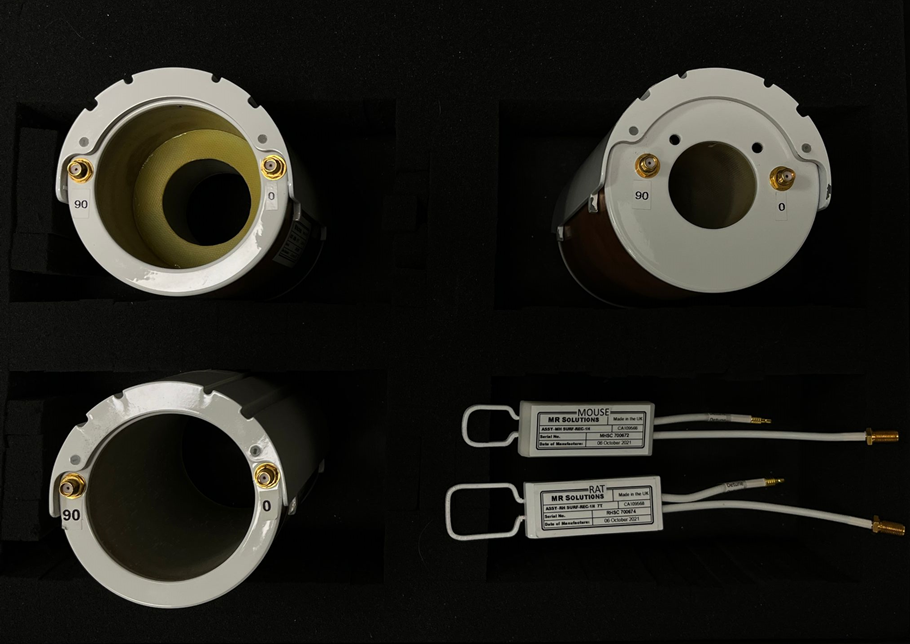

Rat ve farelerde beyin ve vücut görüntüleme işlemleri rat beyin, rat vücut ve fare vücut için özelleşmiş alıcı-verici (Tx/Rx) quadrature sargılar ile gerçekleştirilmektedir ve ayrıca alıcı yüzeyel sargılar da mevcuttur.